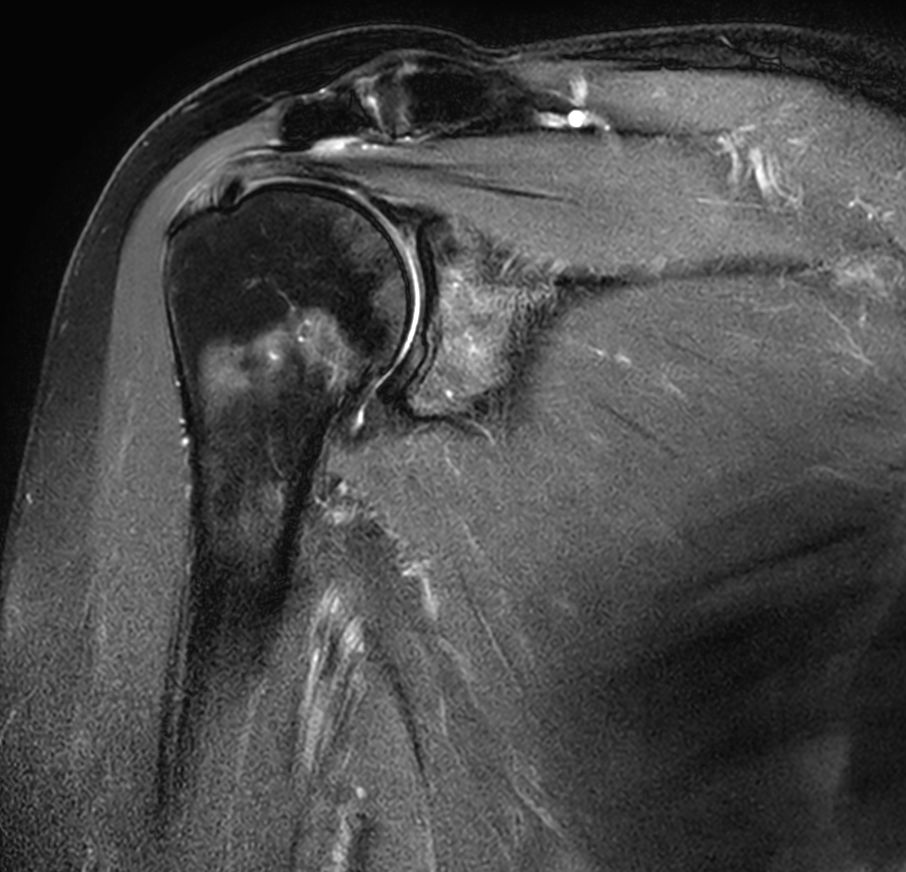

Axial PDw SPAIR